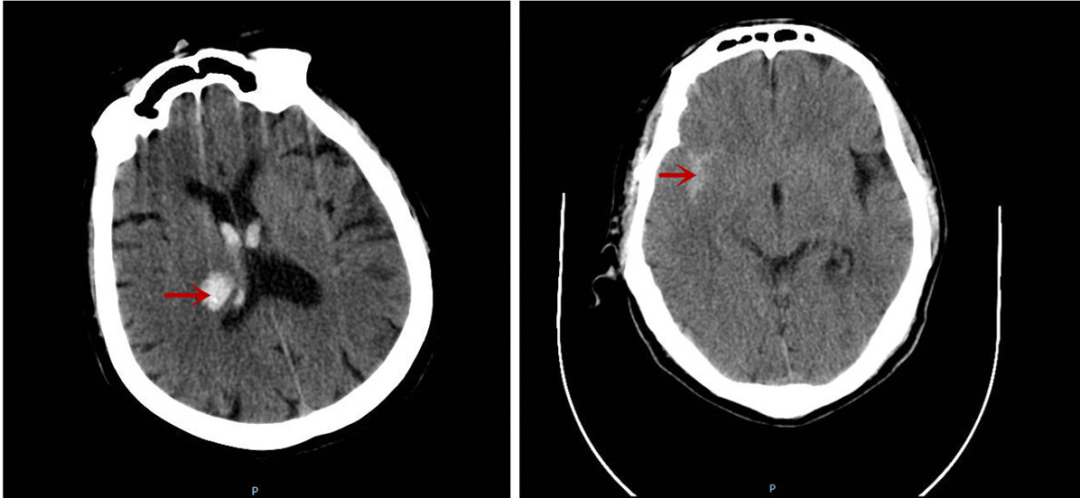

据悉,这两位患者在送医时分别呈现突发头痛伴头晕、突发肢体活动障碍等症状,经急诊颅脑CT检查,一位确诊为丘脑出血,另一位为蛛网膜下腔出血。

图中所示分别为丘脑出血及蛛网膜下腔出血情况